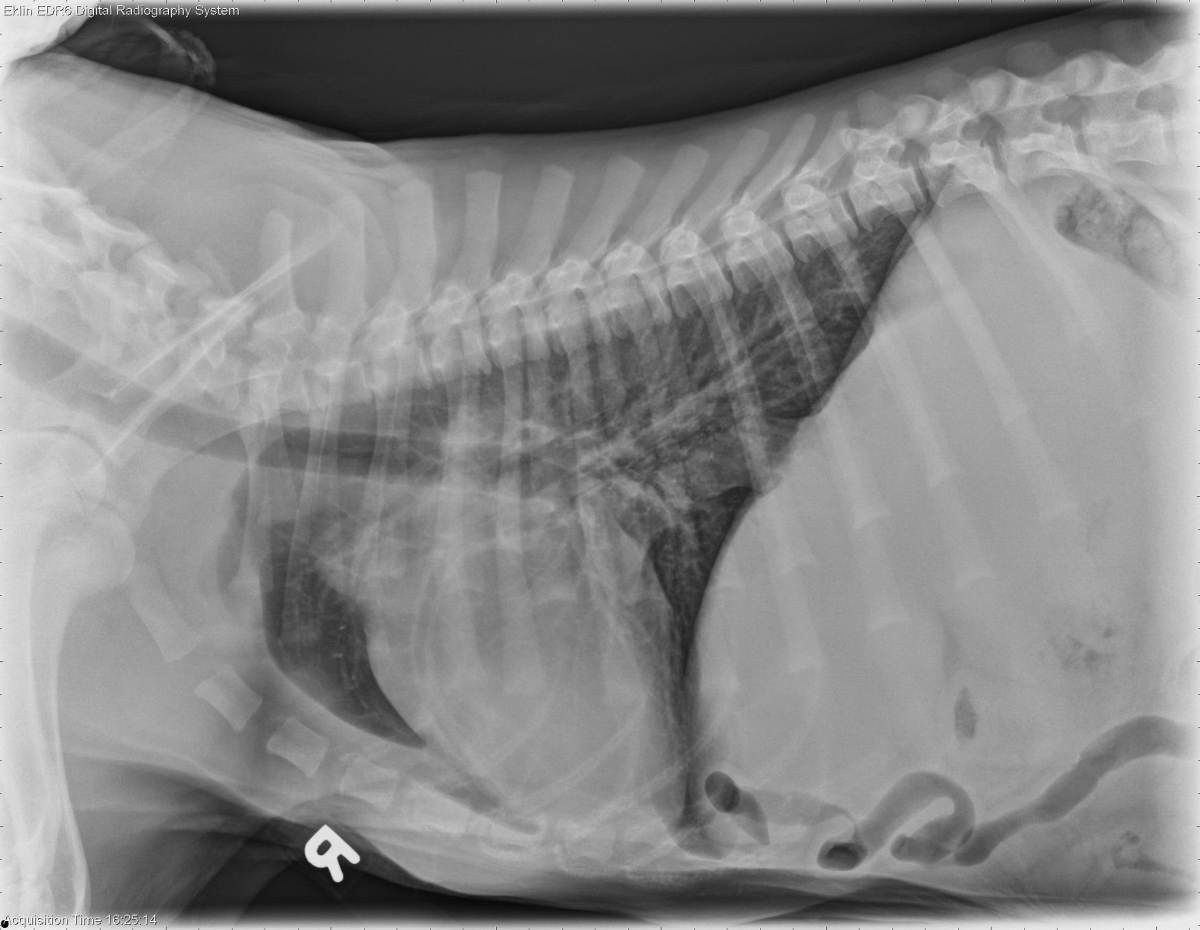

4.5 month old German Shepherd

Today’s case is a 4.5 month old German Shepherd with abdominal distension and heart murmur. This case is challenging!

R LAT Thorax

The heart is moderately enlarged predominantly on the right side. The pulmonary arteries and veins appear mildly distended. There is increased opacity in the region of the aorta and main pulmonary artery on the dorsoventral projection. The caudal vena cava is enlarged and slightly tortuous on both projections. There is poor peritoneal detail and abdominal distension. The pulmonary parenchyma is normal. There is a soft-tissue swelling on the left thoracic wall consistent with recent surgery.

Differential Diagnosis

• Right heart failure due to congenital cardiac anomaly, such as cor triatriatum dexter.

• Mild pulmonary overcirculation may be secondary to previous PDA

• Right-sided cardiomegaly due to pulmonic stenosis.

Diagnosis

• Cor triatriatum dexter. A membrane separating the right atrium into two chambers was seen on echocardiogram. This was corrected with balloon dilation.

• Moderate pulmonic stenosis

• Adequate ligation of the PDA with minimal residual flow